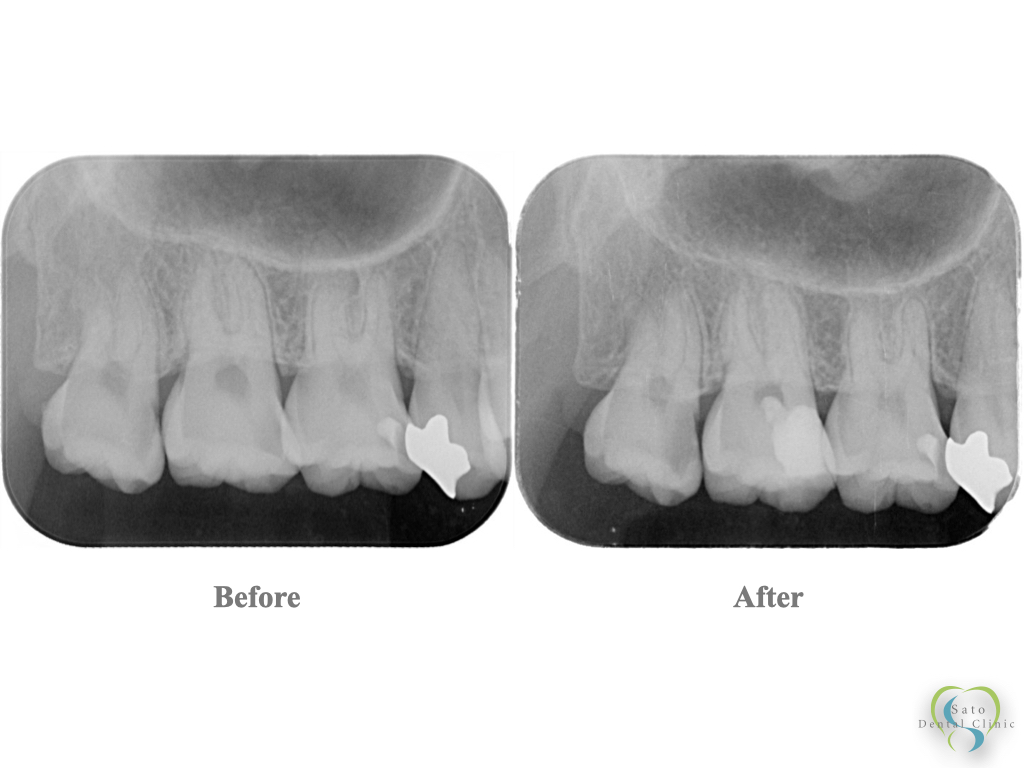

治療前後の比較(レントゲン所見)

治療前のレントゲンでは、歯髄に近接した大きなむし歯が確認できます。

治療後はMTAとレジンによりしっかりと密閉され、歯髄の保護がなされている状態です。今後は定期的に経過を観察し、歯髄の生活反応や根尖部の変化をチェックしていきます。

(右上親知らずは抜歯、第一大臼歯はこの後同様に処置を行う予定です)